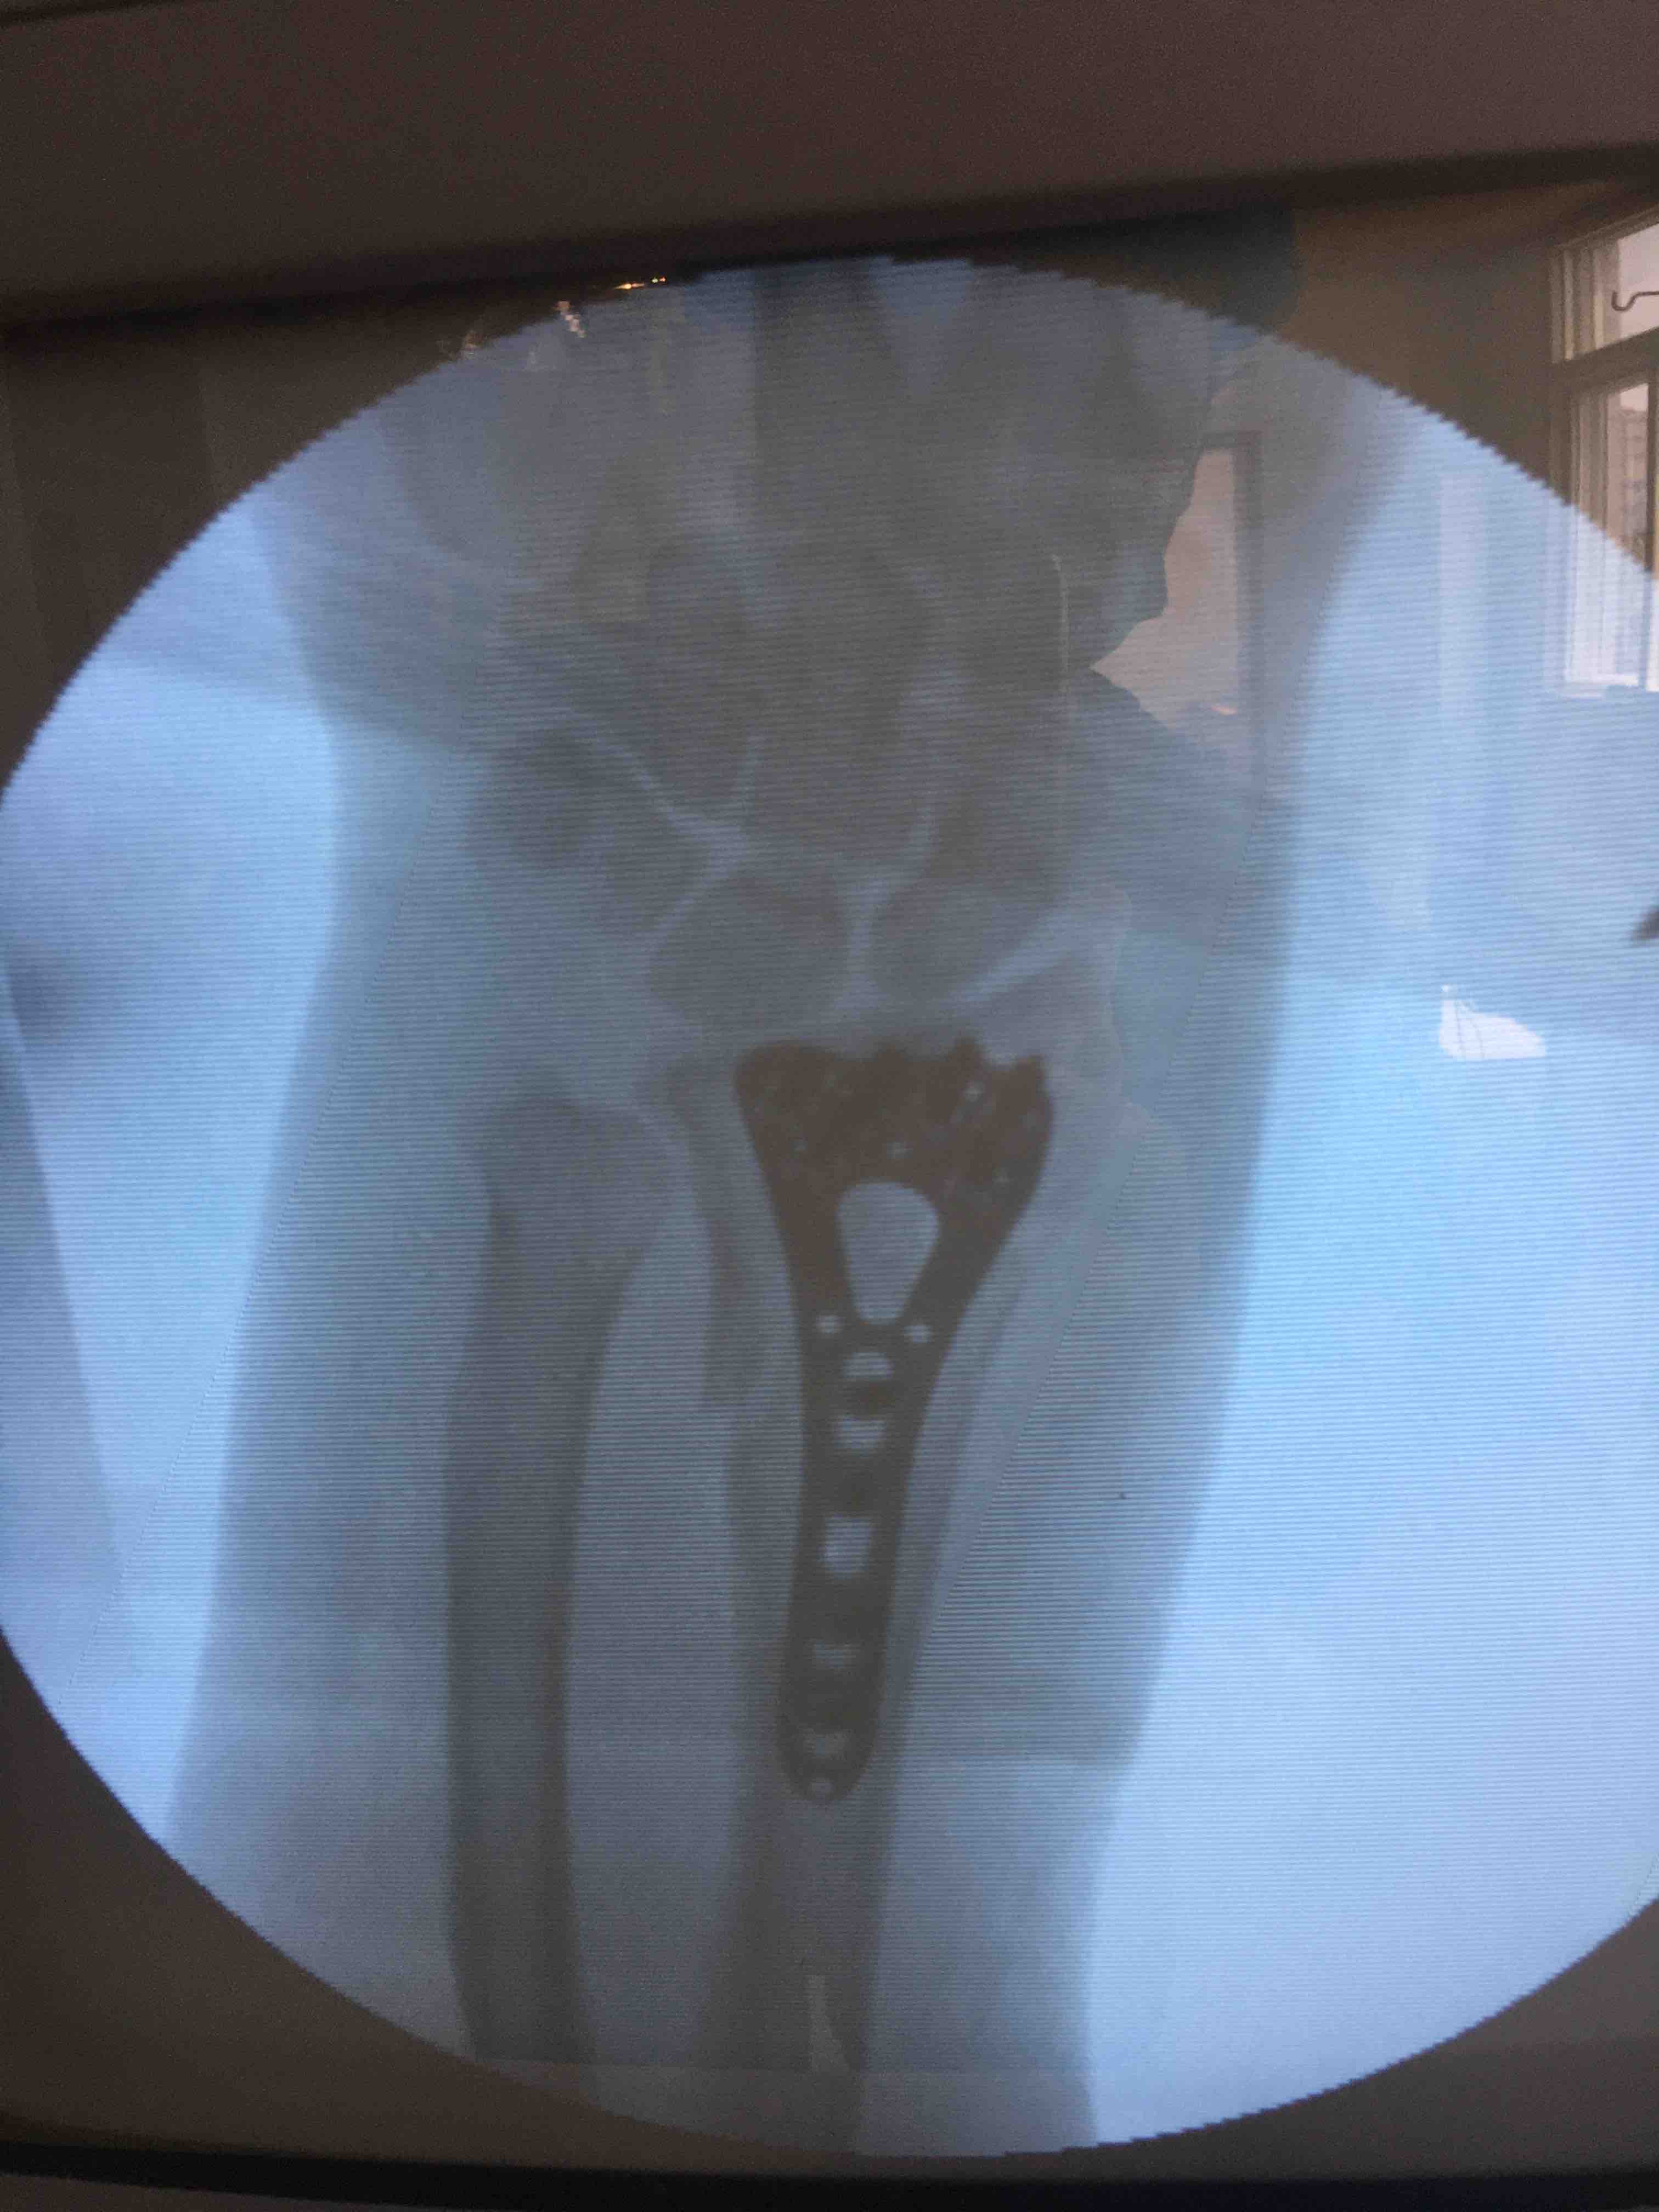

切开复位内固定术,术后抗炎,消肿等处理。